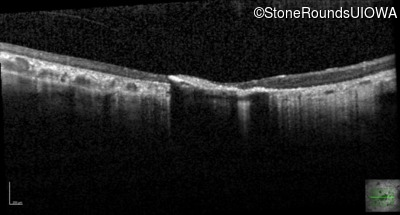

Optical Coherence Tomography - Right - 20/150 sc

Exemplar / OCT Stack